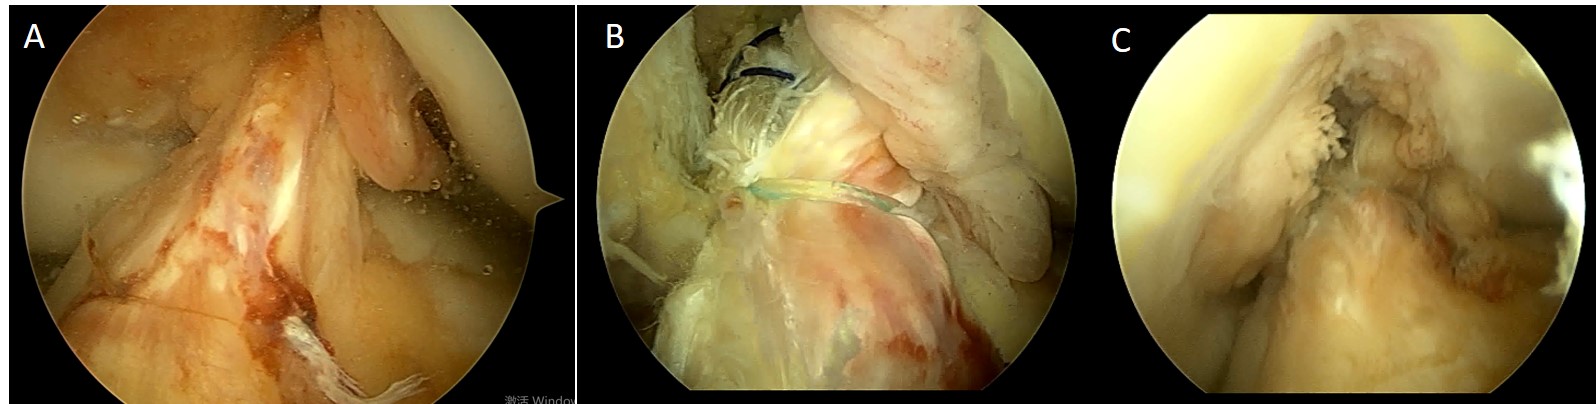

图 前交叉韧带断裂 可见残端

重建的前交叉韧带